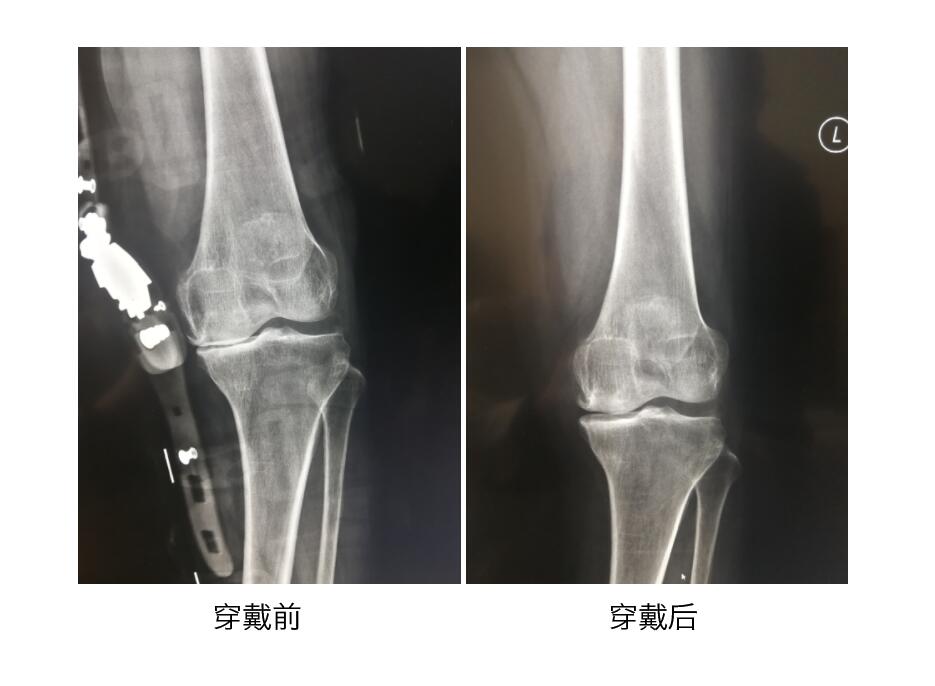

膝关节骨性关节炎支具

矫正受损膝关节 / 降低膝关节负重 / 减轻膝关节疼痛